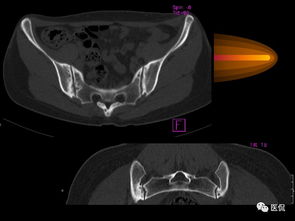

强直性脊柱炎是一种慢性炎症性风湿性疾病,主要侵犯脊柱和骶髂关节,严重时可导致脊柱强直和功能丧失。兰州蜀草中医医院在治疗强直性脊柱炎方面积累了丰富经验,形成了系统完善的中医诊疗方案。